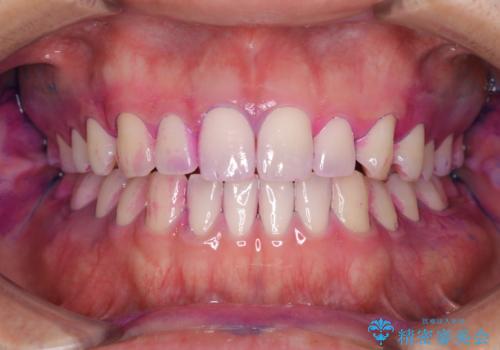

染め出しをして磨き残しのチェックと歯のクリーニング

染め出し液を使ってプラークを染め出すことにより、普段の歯みがきで磨き残している場所を目で確かめることができます。